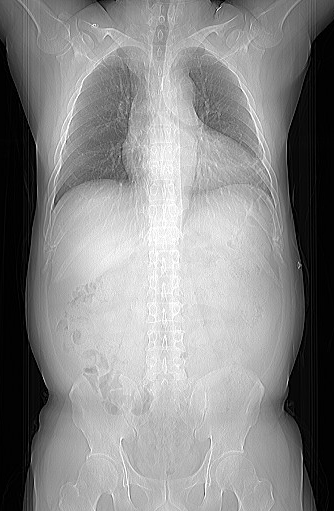

▲ 胸腹连扫、快速完成

同类CT中的佼佼者,扫描1周仅需0.35秒,旋转一圈可以获得128层图像,5秒内完成无创心脏检查,10秒内完成全身检查,且每次扫描辐射剂量及低。冠状动脉CTA使无创冠脉检查成为现实:短短数秒之内便可得到清晰,准确的冠脉影像,快速无创的诊断冠脉狭窄、斑块等病变。这意味着患者在受到尽可能少的辐射暴露的同时,医生也能迅速获取高质量的影像资料,从而加快诊断流程,为及时治疗赢得宝贵时间。